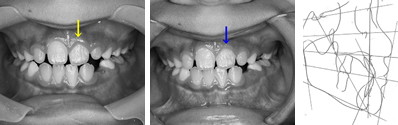

パノラマレントゲンで前歯部分に過剰歯などの異常が無いことを確認。セファログラムレントゲンの分析から、左上の1番目の永久歯(中切歯)が内側に入っていることが問題であることを確認。

上顎左側の2番目の永久歯(側切歯)が反対咬合です。まだ乳歯も多く残る歯並びですが、全体に凸凹が認められます。

一見すると、あまり難しい反対咬合には見えませんが、実は下あごを無理に後ろに押し下げている状態で普段過ごしています。そのため、顎の関節に不具合が生じていました。

また、上顎には一部乳歯が残っているのですが、もう抜けそうになっていたので、その隙間をどうするかも問題となっていました。それに加え、上顎の2番目の永久歯(側切歯)が通常より幅が狭い「矮小歯」だったので、隙間が開いているなどの問題も重なっていました。

さまざまな問題をふくんでいたので、最新のCAD技術を応用した矯正治療分析ソフトを用いて治療計画を立てて、動画で治療経過予測を説明しています。

こちらに示しているのは治療開始時、手術直前予測、手術後予測の3段階静止画像ですが、実際のCADでは治療経過を動画で表現しています。